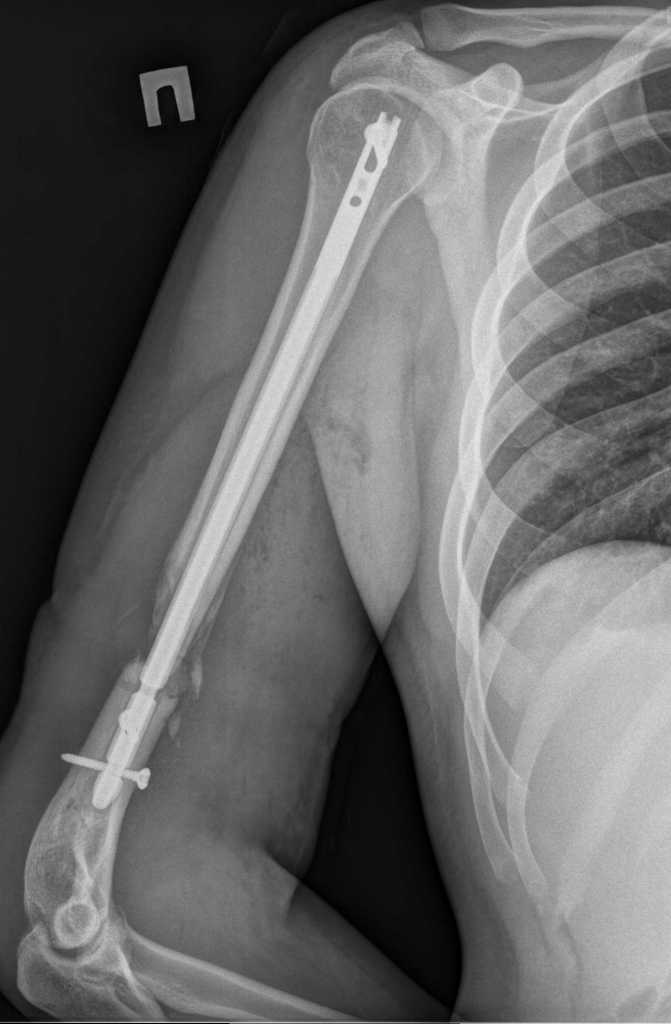

Здравствуйте. Открыто удалили дистальный фрагмент. После рассверливания заштифтовали более массивным штифтом. Спасибо за участие в обсуждении случая.

Имя     : Koval'chuk^A.V.00000.jpg